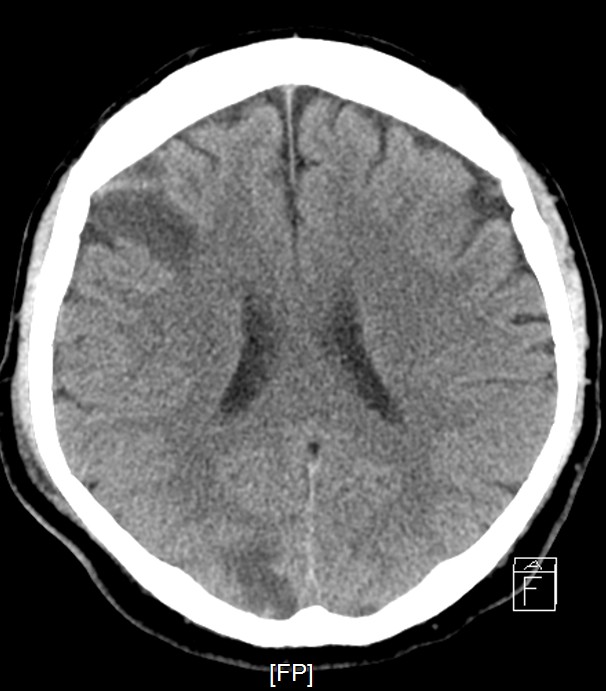

Staged PCI (Mar 6): One DES was placed in the LCX and one DCB in the LM–LCX segment. ECMO and IABP were successfully removed on March 8. Continuous renal replacement therapy was started for acute kidney injury. Brain CT showed watershed infarcts and a small subarachnoid hemorrhage, followed by gradual neurological recovery.